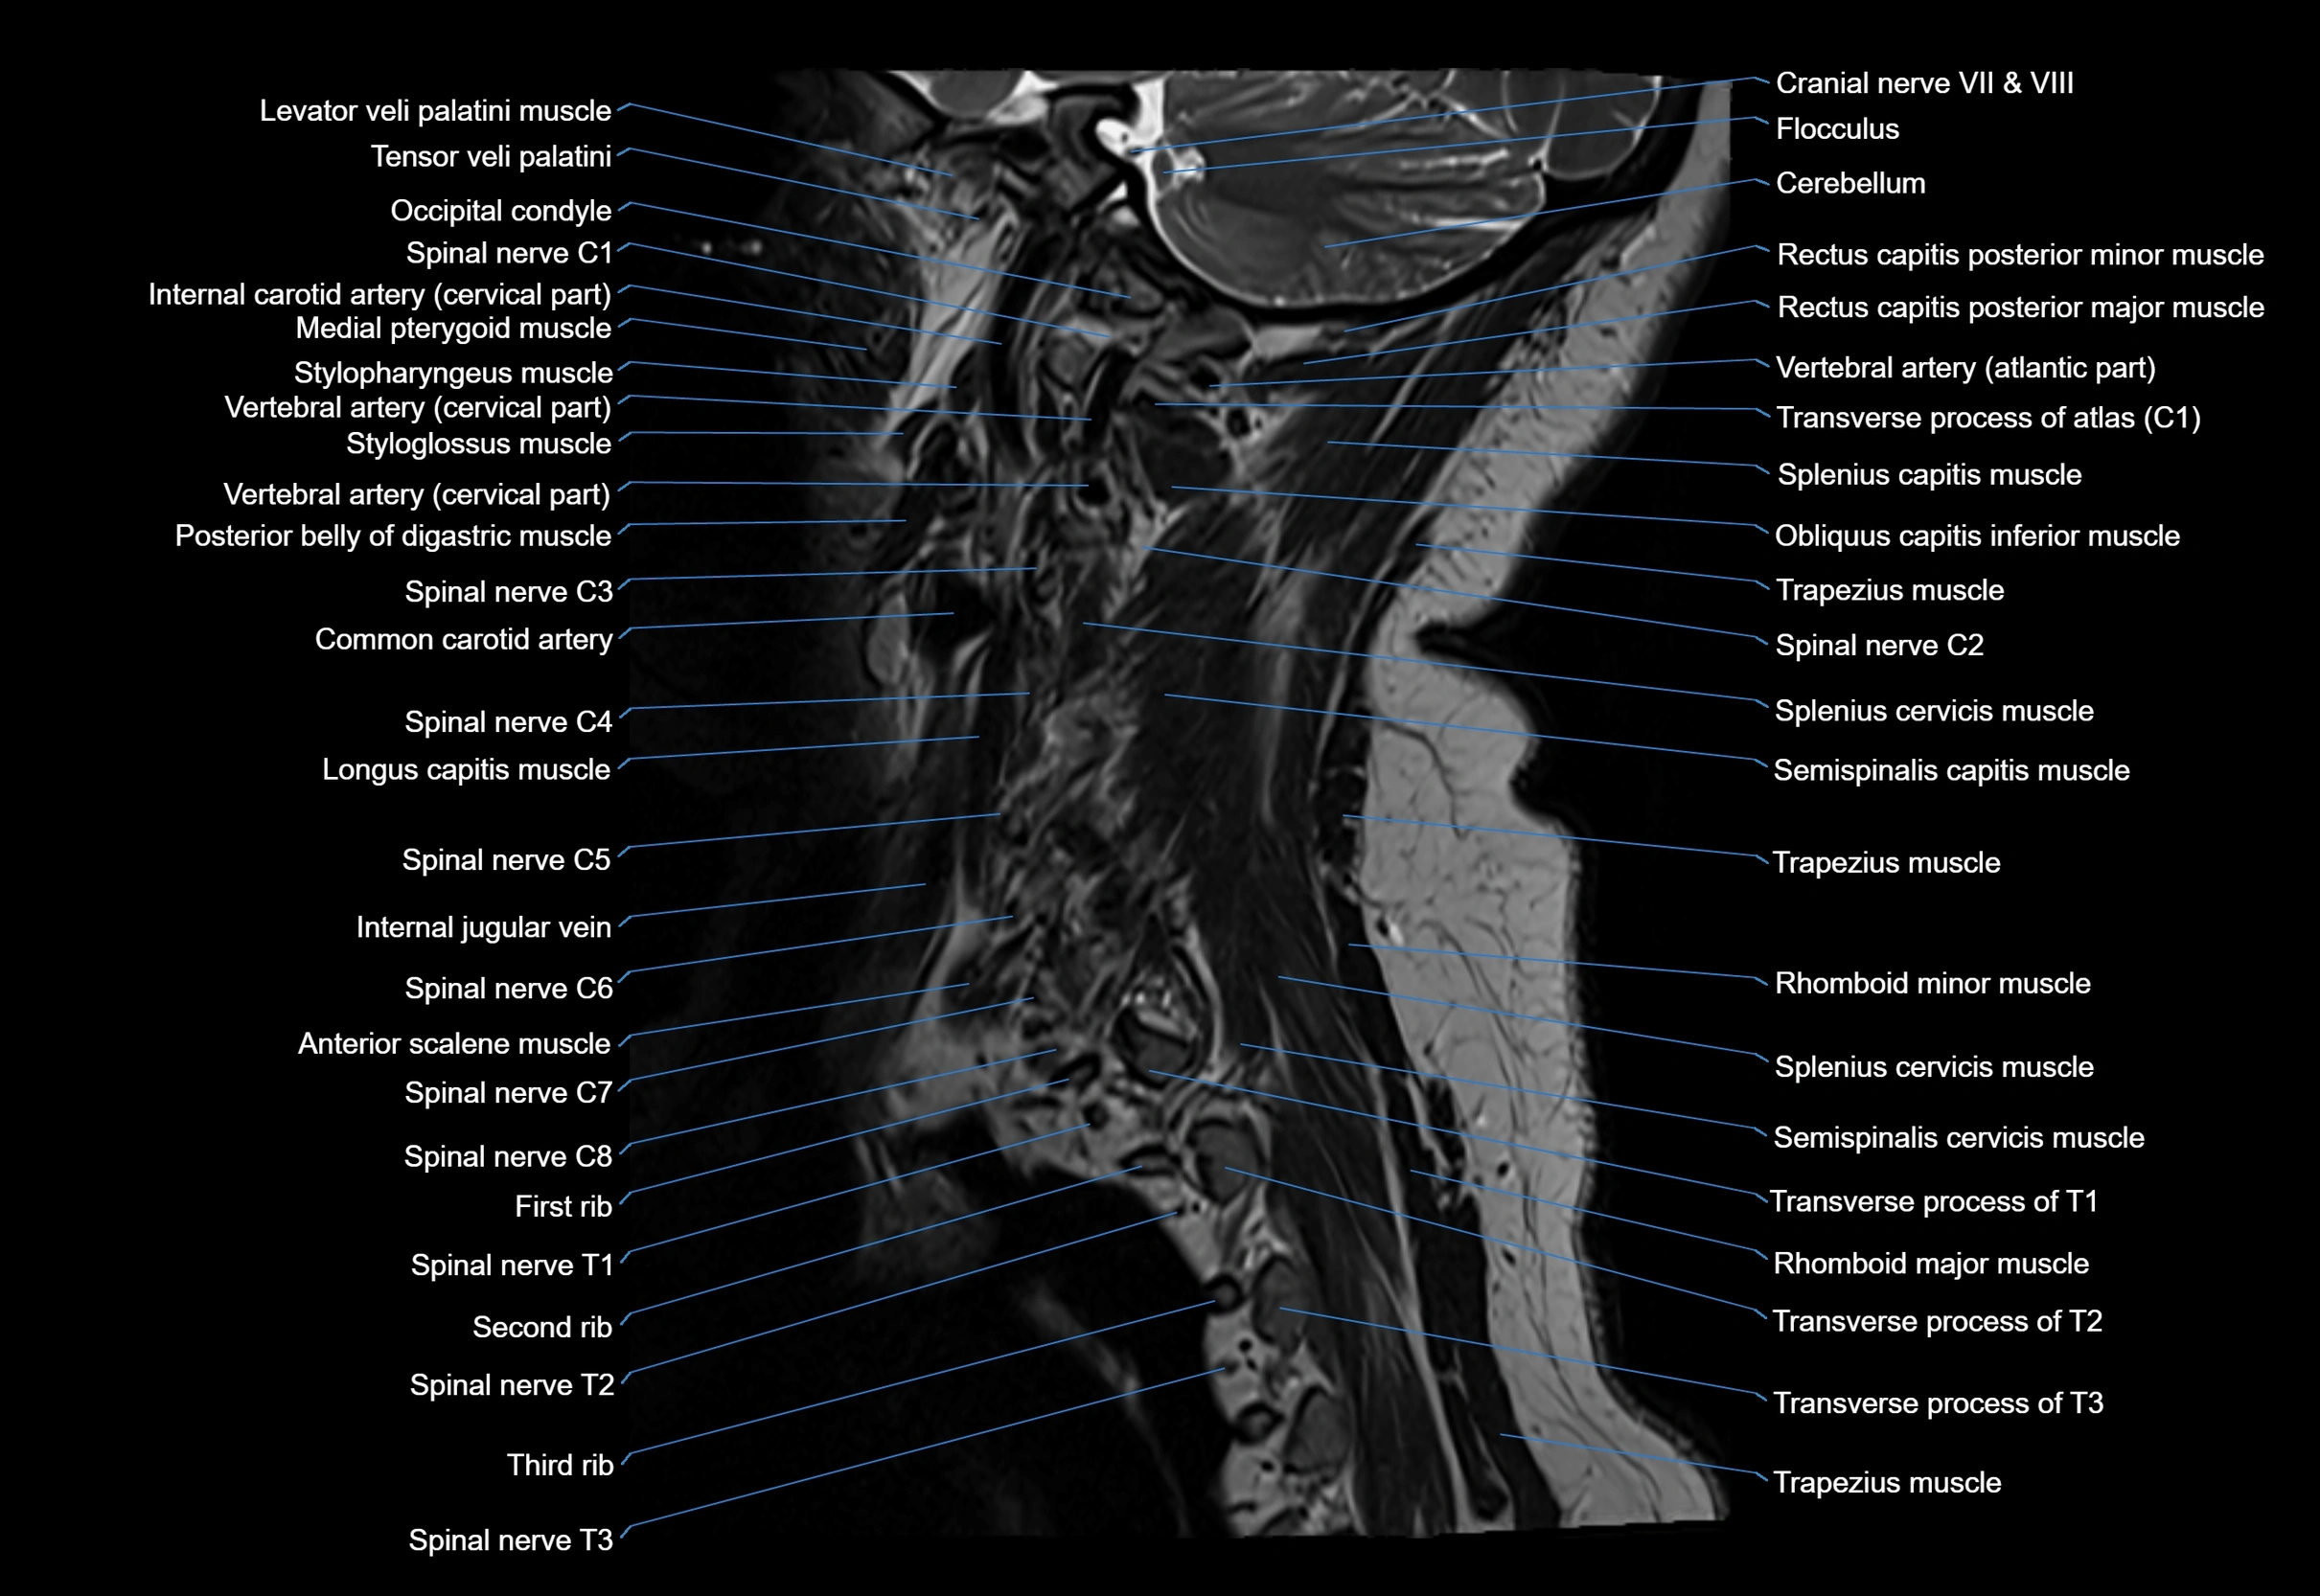

MRI image

image